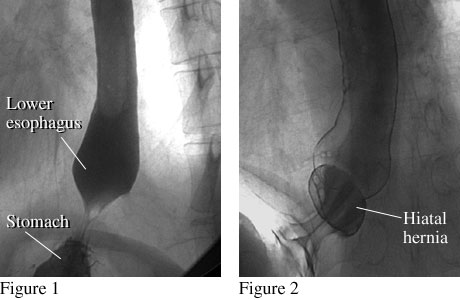

X-ray images after a barium swallow showing a normal esophagus and an esophagus with a hiatal hernia

Figure 1 shows the lower end of a normal esophagus with a smooth connection between the lower esophagus and stomach. Figure 2 shows the lower end of the esophagus with a small hiatal hernia, which occurs when a small portion of the stomach pushes up into the chest.